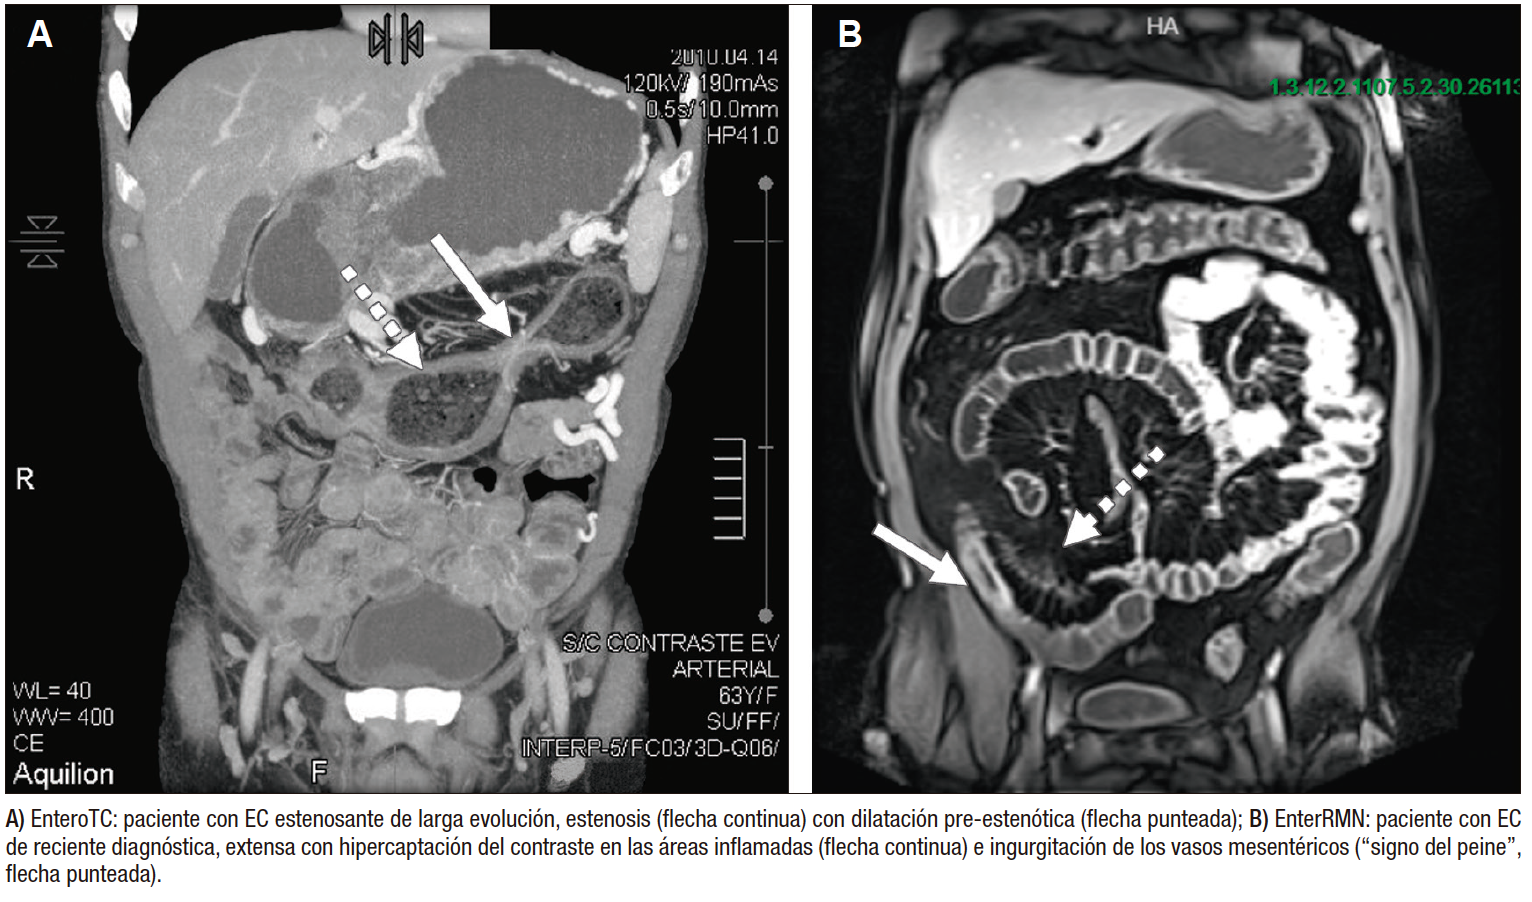

Tanto la e-TC como la e-RMN son modalidades aceptables para diagnosticar inflamación del ID en la EC. Ambas requieren que el paciente se prepare con laxantes previamente y beba un gran volumen de contraste neutro, que se utiliza para distender el intestino y resaltar trastornos intraluminales como inflamación, estenosis y úlceras. También permiten identificar hallazgos extraluminales como fístulas y engrosamiento mesentérico. Hasta el 50% de los casos de EC con colonoscopia normal tienen anormalidades en las imágenes, lo que destaca su utilidad en el diagnóstico de EC.39 Un metaanálisis incluyendo 913 pacientes mostró que la sensibilidad y la especificidad para diagnóstico de EC en ID fueron 87% y 91% respectivamente para la e-TC, y 86% y 93% respectivamente para la e-RMN.40 Al determinar qué modalidad de imagen es mejor para un paciente individual, es importante tener en cuenta las fortalezas y debilidades de cada una.

Debido a que la radiación acumulada resultante de exposiciones repetidas puede entrañar un mayor riesgo de cáncer,41 se sugiere preferir la RMN si está disponible, sobre todo teniendo presente que los pacientes con EII suelen ser jóvenes con requerimiento de varios estudios a lo largo de su vida. El uso actual de la TC está vinculado principalmente a situaciones de urgencia, ya que es un método rápido cuyo uso se sugiere ante la sospecha de complicaciones, punción guiada de colecciones o cirugía urgente altamente probable a la brevedad. La e-RMN es el método actual de elección por lo antes mencionado, sin embargo el paciente debe estar alertado de que el estudio dura más de 1 hora y requiere que el paciente permanezca quieto en un lugar muy cerrado, lo cual es muy difícil de lograr en algunos casos. La e-RMN tiene la ventaja asociada de poder realizar cortes de pelvis, fundamentales para la evaluación de la enfermedad perianal con un de 97% de sensibilidad y un 96% de especificidad en el diagnóstico de fístulas anales.42

Dentro de los cambios murales que pueden detectarse con la e-RMN se encuentran el engrosamiento de la pared, la captación del contraste endovenoso en la mucosa inflamada, úlceras, edema de la pared, estenosis, dilataciones e infiltración grasa de la pared. Los hallazgos extramurales incluyen fístulas, tractos sinusales, abscesos, “signo del peine” -que traduce la ingurgitación de los vasos que irrigan la pared inflamada-, adenopatías y proliferación grasa en el mesenterio. Figura 4.

Figura 4. Imágenes en EII

Existen varios scores para monitoreo de actividad y respuesta a los tratamientos guiados por e-RMN. El primero y mejor validado es el Índice de Resonancia Magnética de Actividad (MaRIA), calculado a partir de predictores independientes tanto de la presencia de inflamación endoscópica (engrosamiento de la pared, realce de contraste mural) como de la presencia de ulceraciones endoscópicas (edema mural y ulceración detectada por RMN). Una puntuación MaRIA ≥ 7 indica enfermedad activa y ≥ 11 indican enfermedad grave (ulcerosa).43 Sin embargo, calcular la puntuación MaRIA lleva tiempo debido a que requiere la medición de la intensidad de la señal de la pared intestinal colocando manualmente múltiples regiones de interés. Además, los segmentos normales contribuyen a la puntuación MaRIA global y en pacientes con segmentos resecados se produce una subestimación de la puntuación global. Estos inconvenientes llevaron al desarrollo de la puntuación MaRIA simplificada (sMaRIA), que requiere mucho menos tiempo de cálculo y donde los segmentos normales no cuentan en la puntuación global. El sMaRIA también ha sido validado contra estándares endoscópicos de referencia.44, 45